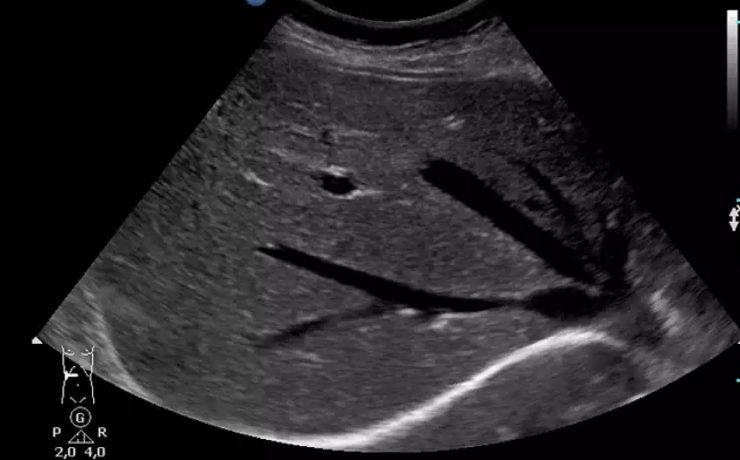

Ectopia renal simple